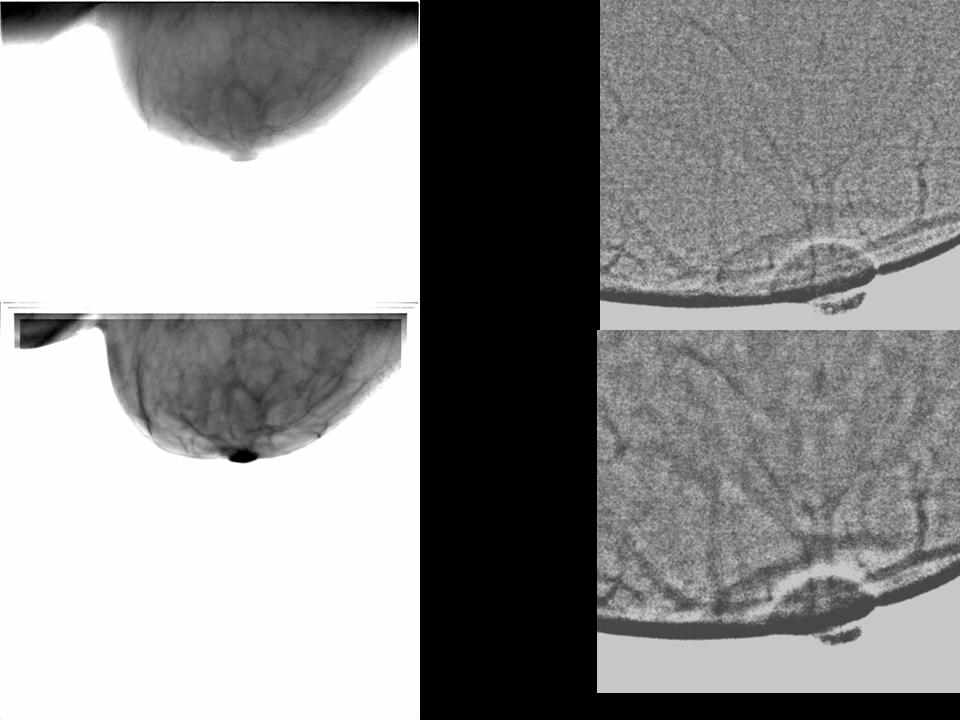

Цифровая маммография

Лучший способ правильно читать маммограммы - позиционировать маммограммы в окне просмотра в зеркальном изображении с просмотрами MLO и CC, установленными сзади

Анализ маммограммы требует качественной визуализации и систематического диагностического подхода, включающего два этапа:

На первом этапе целью является выявление локализованного различного структурного аспекта по сравнению с соседними регионами и контралатеральной грудью.

Второй шаг заключается в анализе этого аспекта, чтобы распознать более или менее физиологические вариации или, наоборот, классифицировать изображение как подозрительное. Изучение нормальной груди может быть затруднено, особенно для молодых женщин, у которых часто бывает плотная и нерегулярная грудь.